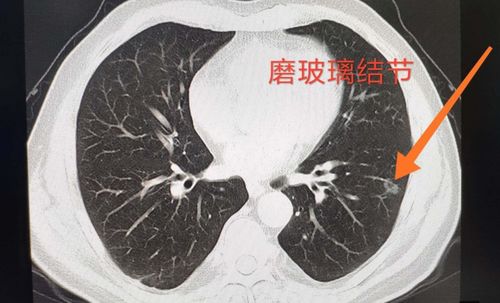

女子肺部磨玻璃结节癌变理赔遭拒:保险公司拒赔是否合理? 90后张小姐被诊断有肺部磨玻璃结节,之后其所在公司为员工购买了团体重疾险,后来张小姐的磨玻璃结节癌变,却遭保险公司拒赔。本文详细分析了该案件的经过及法律判决。 百度热点 2024年11月20日 09:35 0 点赞 0 评论 63 浏览